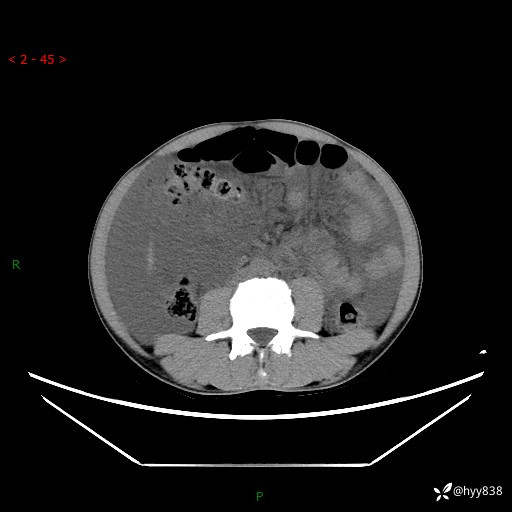

现病史:患者10天前无明显诱因出现腹部胀痛不适,无畏寒发热,无胸痛胸闷,无心慌气短,无恶心呕吐,无腹泻及黑便,无粘液血便及里急后重等症状,4天前在当地县人民医院就诊,行腹部CT示:下腹部占位性病变,腹腔及盆腔积液;今患者为求进一步诊治来我院治疗,门诊以“腹水”收治入院。 发病以来,精神饮食可,大小便正常,体重体力无明显变化。

腹部CT平扫+增强